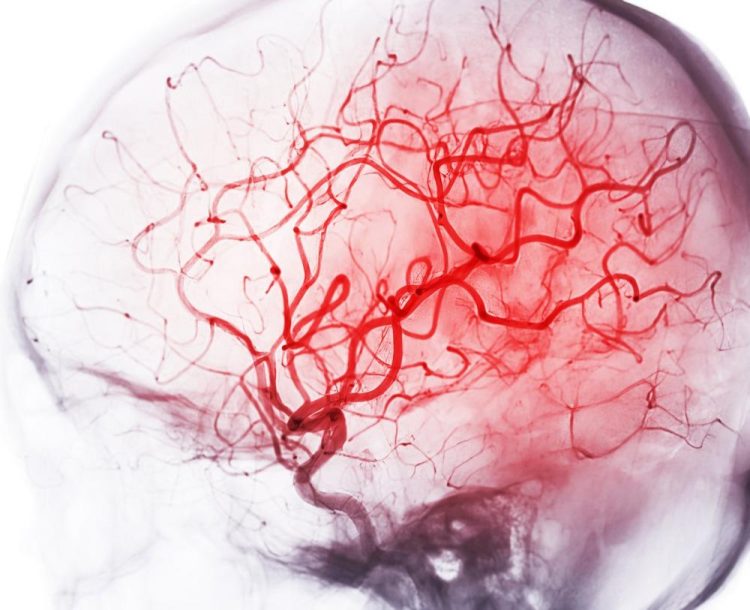

Ein juveniler Schlaganfall, also ein Schlaganfall bei Kindern, Jugendlichen und jungen Erwachsenen, stellt eine besondere ärztliche Herausforderung dar. Um die Symptome bei jungen Betroffenen richtig zu erkennen, die Ätiologie zu klären und eine zielgerichtete Therapie einzuleiten, bedarf es besonderer Expertise und Erfahrung.

- Hirnblutungen und Gefäßmalformationen

- Die Moyamoya-Angiopathie als Ursache des juvenilen Schlaganfalls